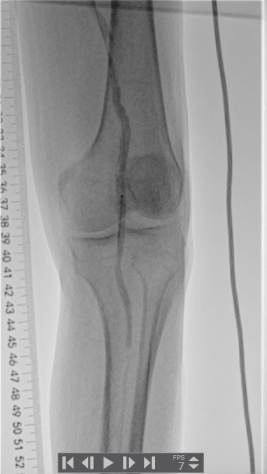

左侧小腿中下段皮温低

左腘动脉、足背、胫后动脉未扪及搏动

足趾颜色紫绀,血运差

术前下肢动脉CTA提示:左下肢股、腘动脉长段闭塞,膝下动脉主干未见显影,可见少量侧支血流。